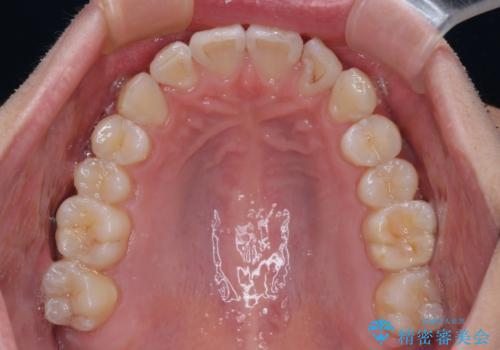

前歯のデコボコをインビザラインで綺麗に改善

- 上下前歯のデコボコとクロスバイトを気にして来院された患者様です。

インビザラインを用い、IPR(歯と歯の間を削る)と歯列全体を拡大させることで、歯並びを整えていくこととしました。

毎日22時間の装着時間を徹底してくださったのですが、左右ともに臼歯が咬合しなくなるという、インビザライン独特の症状が強く長く続いてしまい、終了するまでに長期間を要してしまいました。